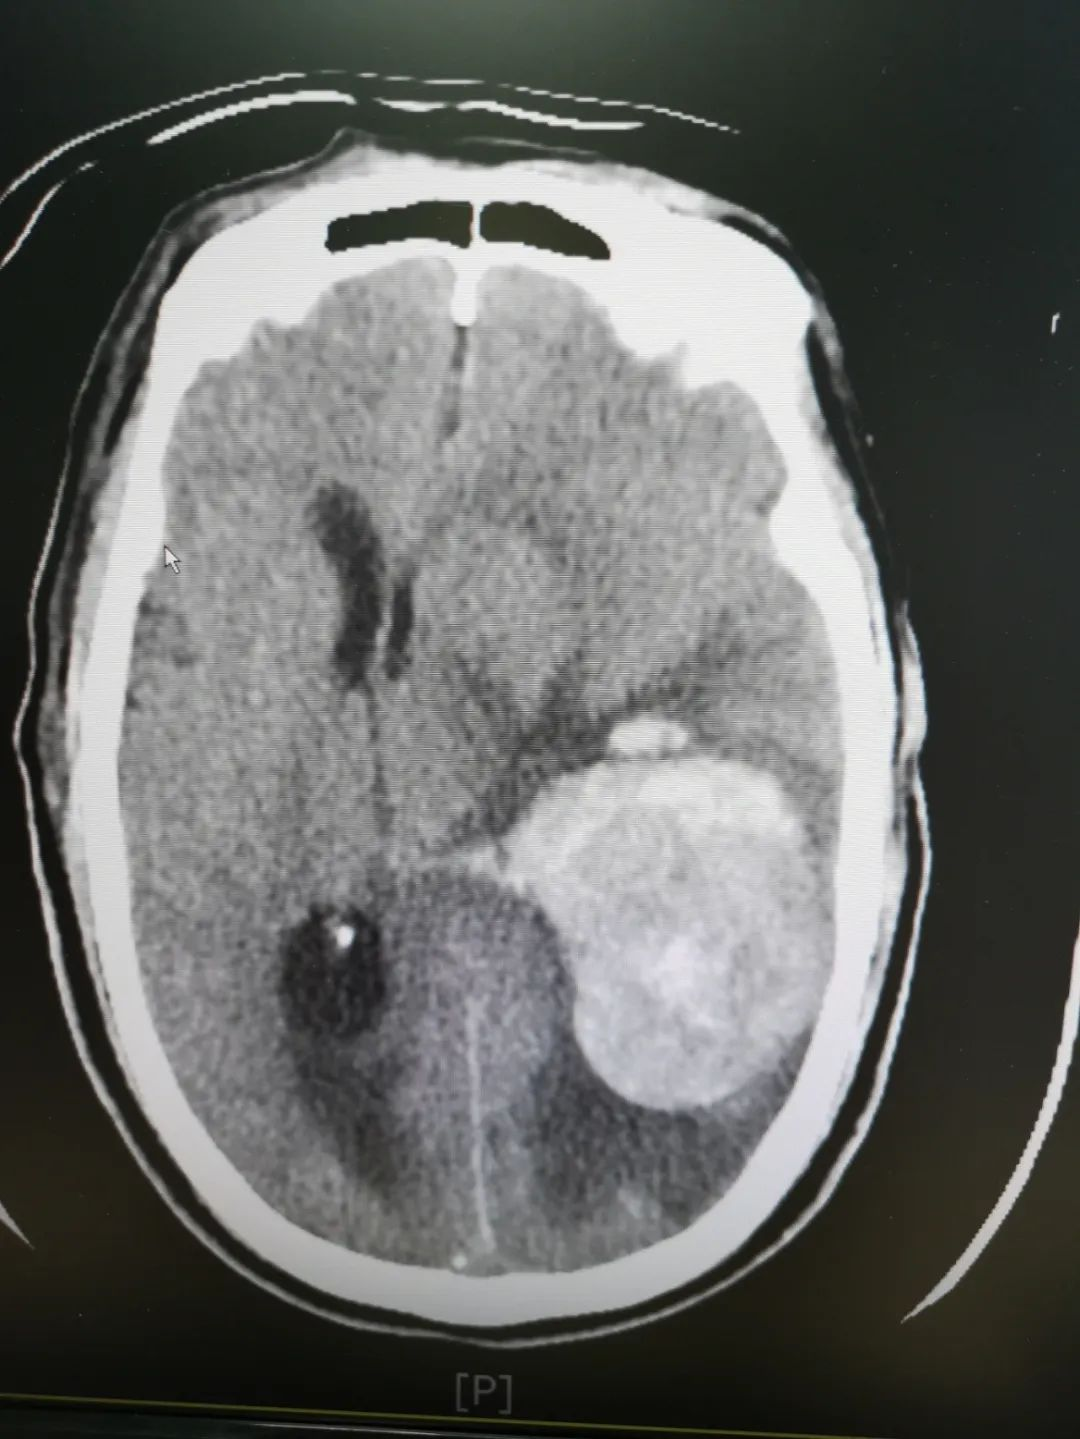

患者,张叔,72岁,长期罹患高血压,未坚持服药,且是一位独居老人。自2022年3月13日始,家属连续2天都无法联系上他,回家后才发现张叔已经处于昏迷状态,遂紧急送当地医院就诊,因病情危重,立即通过卒中中心绿色通道转诊我院。来院时患者有呼吸困难、已处于休克状态,予以气管插管、呼吸机辅助通气、扩容补液等紧急救治后,完善头颅CT检查提示“左侧颞顶叶急性脑出血(血肿量约75ml)伴少量破入脑室,大脑镰下疝形成”。神经外科杨建雄科主任、叶志其副主任迅速组织手术团队展开病情讨论。大家认为:患者高龄,脑出血量多,大脑镰下疝形成,伴低容量性休克,需纠正休克后紧急手术干预,术式选择颅内压监测、内镜下清除血肿,能减少术中出血,迅速降低颅内压力。所有术前准备有条不紊、火速进行,患者由卒中中心救治团队以最快的速度护送手术室进行手术治疗。

术前头颅CT提示左侧颞顶叶急性脑出血